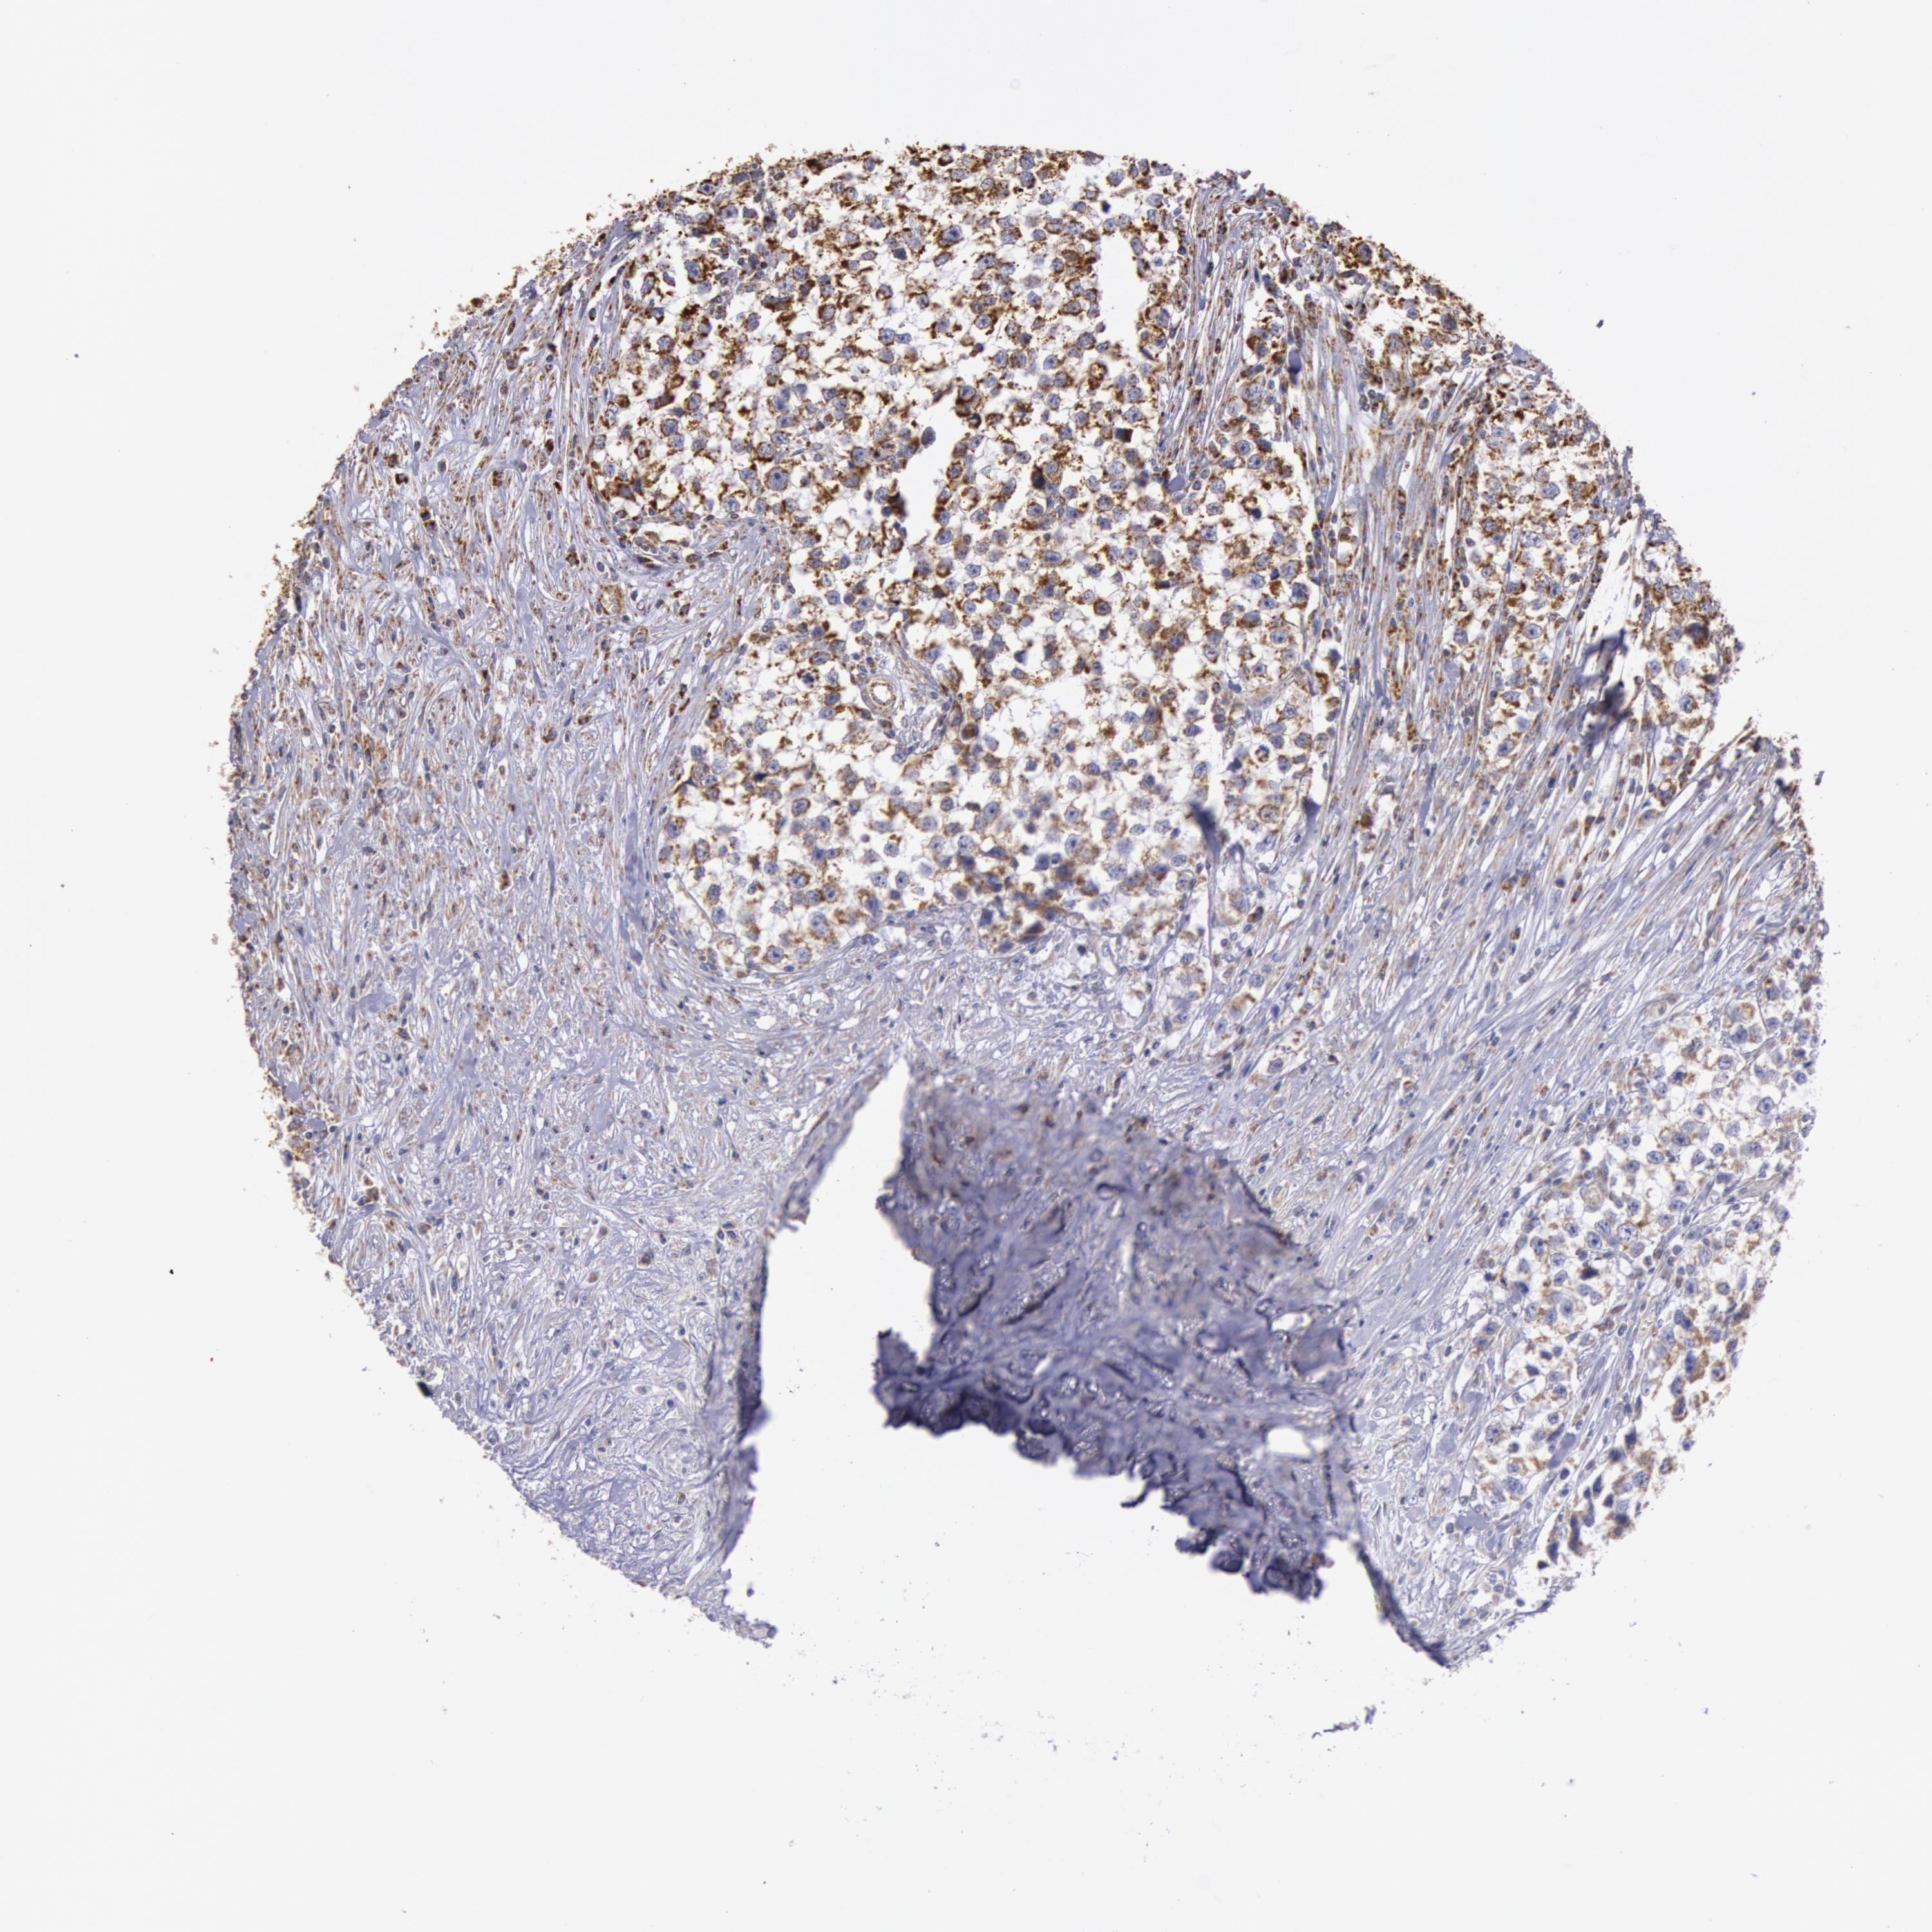

TESTIS CANCER - Protein expressioni

A mouse-over function shows sample information and annotation data. Click on an image to view it in a full screen mode. Samples can be filtered based on level of antibody staining by selecting one or several of the following categories: high, medium, low and not detected. The assay and annotation is described here.

Note that samples used for immunohistochemistry by the Human Protein Atlas do not correspond to samples in the TCGA dataset.

Antibody stainingi

Antibody staining in the annotated cell types in the current human tissue is reported as not detected, low, medium, or high, based on conventional immunohistochemistry profiling in selected tissues. This score is based on the combination of the staining intensity and fraction of stained cells.

Each image is clickable and will lead to virtual microscopy that enables deeper exploration of all samples and also displays staining intensity scores, fraction scores and subcellular localization as well as patient and tissue information for each sample.

Antibody HPA001247

Staining

High

Medium

Low

Not detected

Intensity

Strong

Moderate

Weak

Negative

Quantity

>75%

75%-25%

<25%

None

Location

Nuclear

Cytoplasmic/membranous

Cytoplasmic/membranous,nuclear

Seminoma, NOS

Carcinoma, Embryonal, NOS